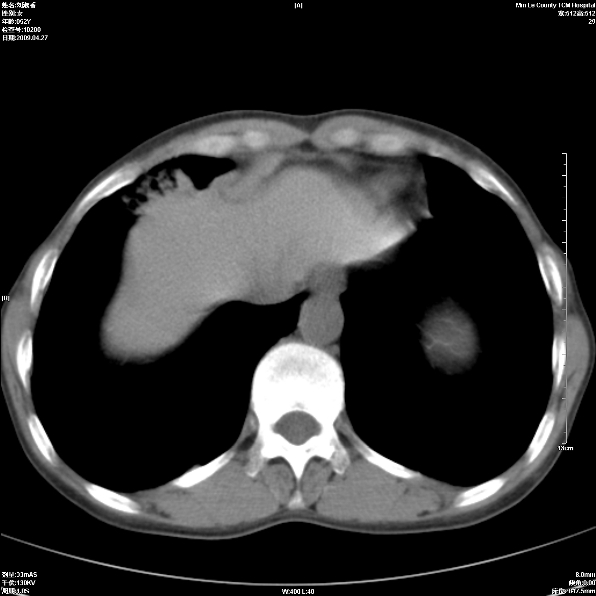

标题: CT19625:女52间断性喀血 [打印本页]

标题: CT19625:女52间断性喀血

考虑右肺中叶感染性病变并右肺中、下叶肺泡积血;建议抗炎、止血治疗后复查。

右肺中叶炎症;右肺中、下叶肺泡积血

右肺中叶支气管扩张并感染或咳血沉积,块右肺中下叶肺泡积血。

右肺中叶慢性炎症伴局部支扩并中下叶肺泡积血。

考虑右肺中叶感染性病变并右肺中、下叶肺泡积血。建议治疗后复查。